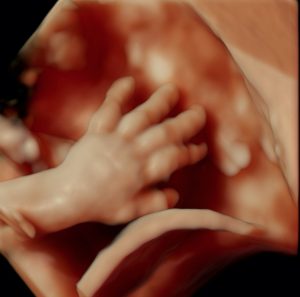

ÉCHOGRAPHIE OBSTÉTRICALE